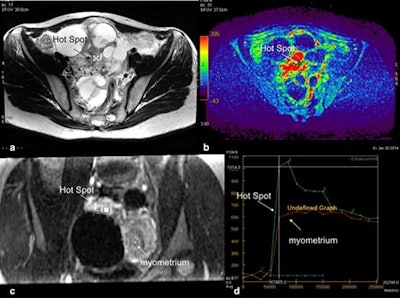

Technical assessment of dynamic contrast-enhanced MR imaging in complex adnexal masses. This example shows a complex right ovarian mass with a solid component in intermediate T2-weighted signal (a) that heterogeneously enhances after gadolinium injection. Parametric map (maximal slope) helps to determine the most suspicious location (hot spot) where the region of interest should be placed to build the time-intensity curve (b). To compare this curve with the myometrial curve, 3D T1-weighted sequence must be reformatted in the coronal plane to place the two regions of interest (solid component and external myometrium) (c). Comparison of time-intensity curves shows the solid component enhances according to a time-intensity curve type 3 (curve steeper than that of myometrium).For the female pelvis, use the urine in the bladder as an internal reference to guarantee the chosen high b-value is satisfactory. The urine is high in signal intensity at b0 and decreases as the b-value increases. When the bladder signal intensity is fully suppressed, the optimal b-value for adnexal mass characterization is achieved, they added.